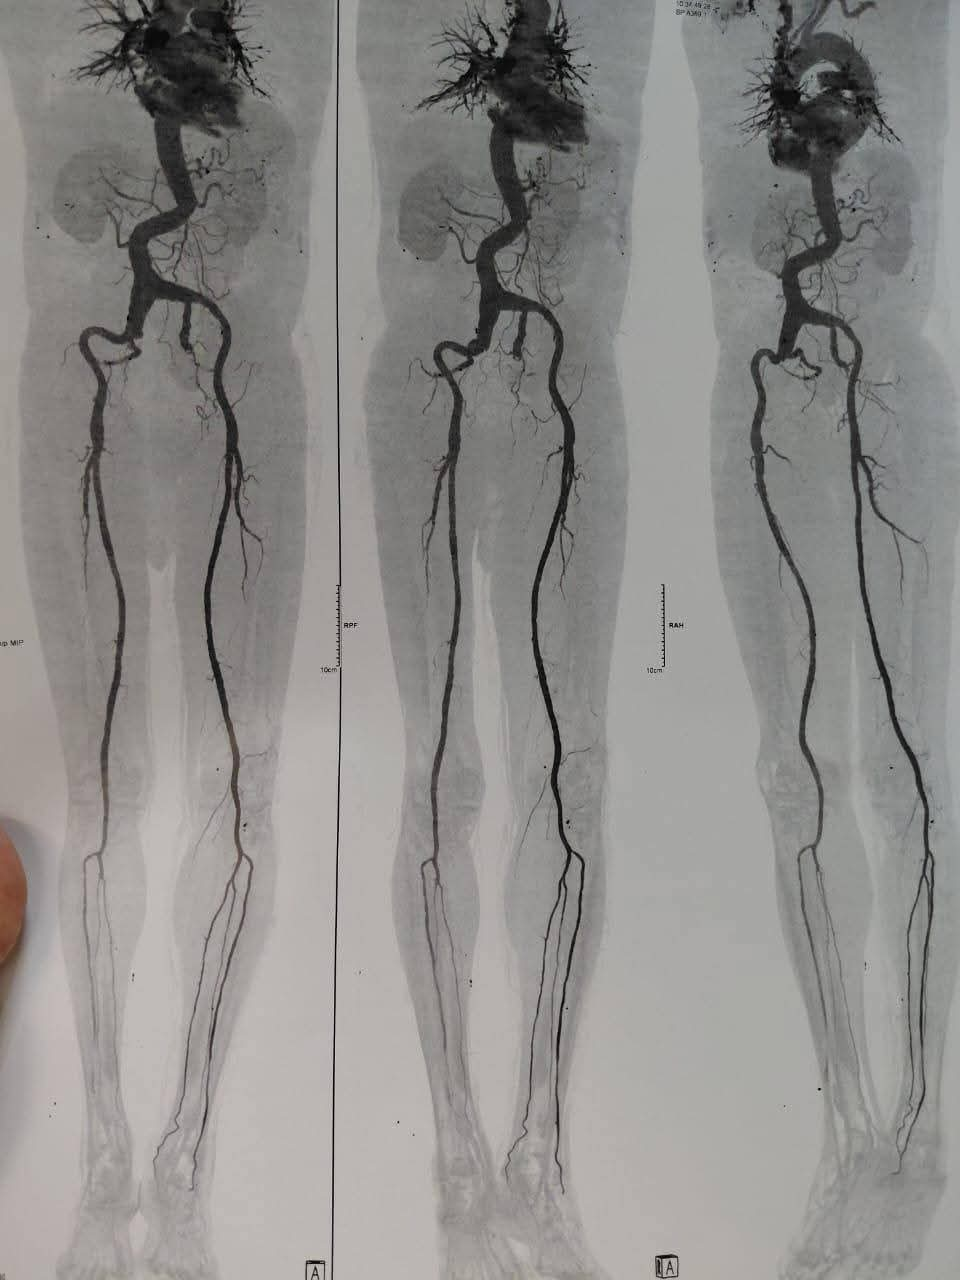

إنجاز طبي جديد يُضاف إلى سلسلة النجاحات التي تحققها جامعة كفر الشيخ في المجال الطبي، حيث نجح فريق جراحة الأوعيه الدمويه بمستشفى الجامعه بإجراء عمليه جراحيه متقدمه لإصلاح تمدد ضخم بالشريان الأورطي البطني والشرايين الحرقفيه بالحوض باستخدام شريان صناعي متفرع، وذلك لأول مرة داخل محافظة كفر الشيخ

يذكر، أن العمليه التي أُجريت بنجاح هي من العمليات الدقيقة والمعقدة جدًا، والمعروفة طبيًا باسم

Aorto bi-iliac bypass with re-anastmosis of IIA using a pantaloon graft for a huge AORTOILIAC aneurysm،

وقد خرجت الحاله بحمد الله بسلام وصحه تامه بعد التعامل مع التمدد الضخم بدقة وكفاءة عالية.